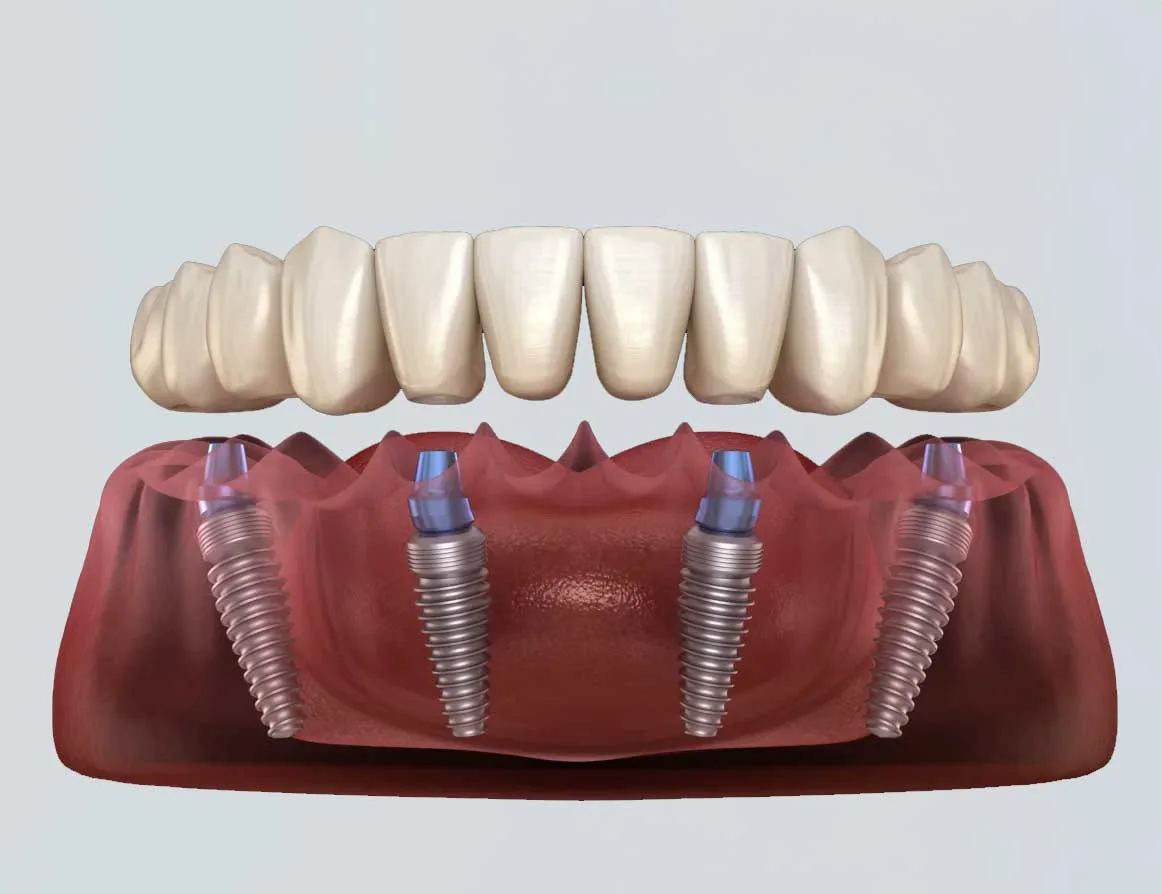

Les implants dentaires représentent aujourd’hui l’une des solutions les plus performantes pour remplacer une ou plusieurs dents manquantes. Ils se composent d’une racine artificielle, généralement en titane, insérée dans l’os de la mâchoire, sur laquelle vient se fixer une couronne ressemblant à une dent naturelle. Durables, confortables et esthétiques, les implants

La réussite d’un implant dentaire repose sur un concept fondamental : l’ostéointégration. Il s’agit de la fusion naturelle entre l’implant et l’os de la mâchoire, garantissant à la fois la stabilité et la durabilité du traitement. À Casablanca, les cliniques spécialisées mettent un accent particulier sur la qualité de l’os et la planification chirurgicale pour assurer le succès de chaque intervention.

Un traitement par implants dentaires est une solution moderne, durable et efficace pour remplacer une ou plusieurs dents manquantes. À Casablanca, comme partout ailleurs, ce traitement se déroule selon des étapes bien définies qui visent à garantir la réussite fonctionnelle, esthétique et biologique de l’implant.